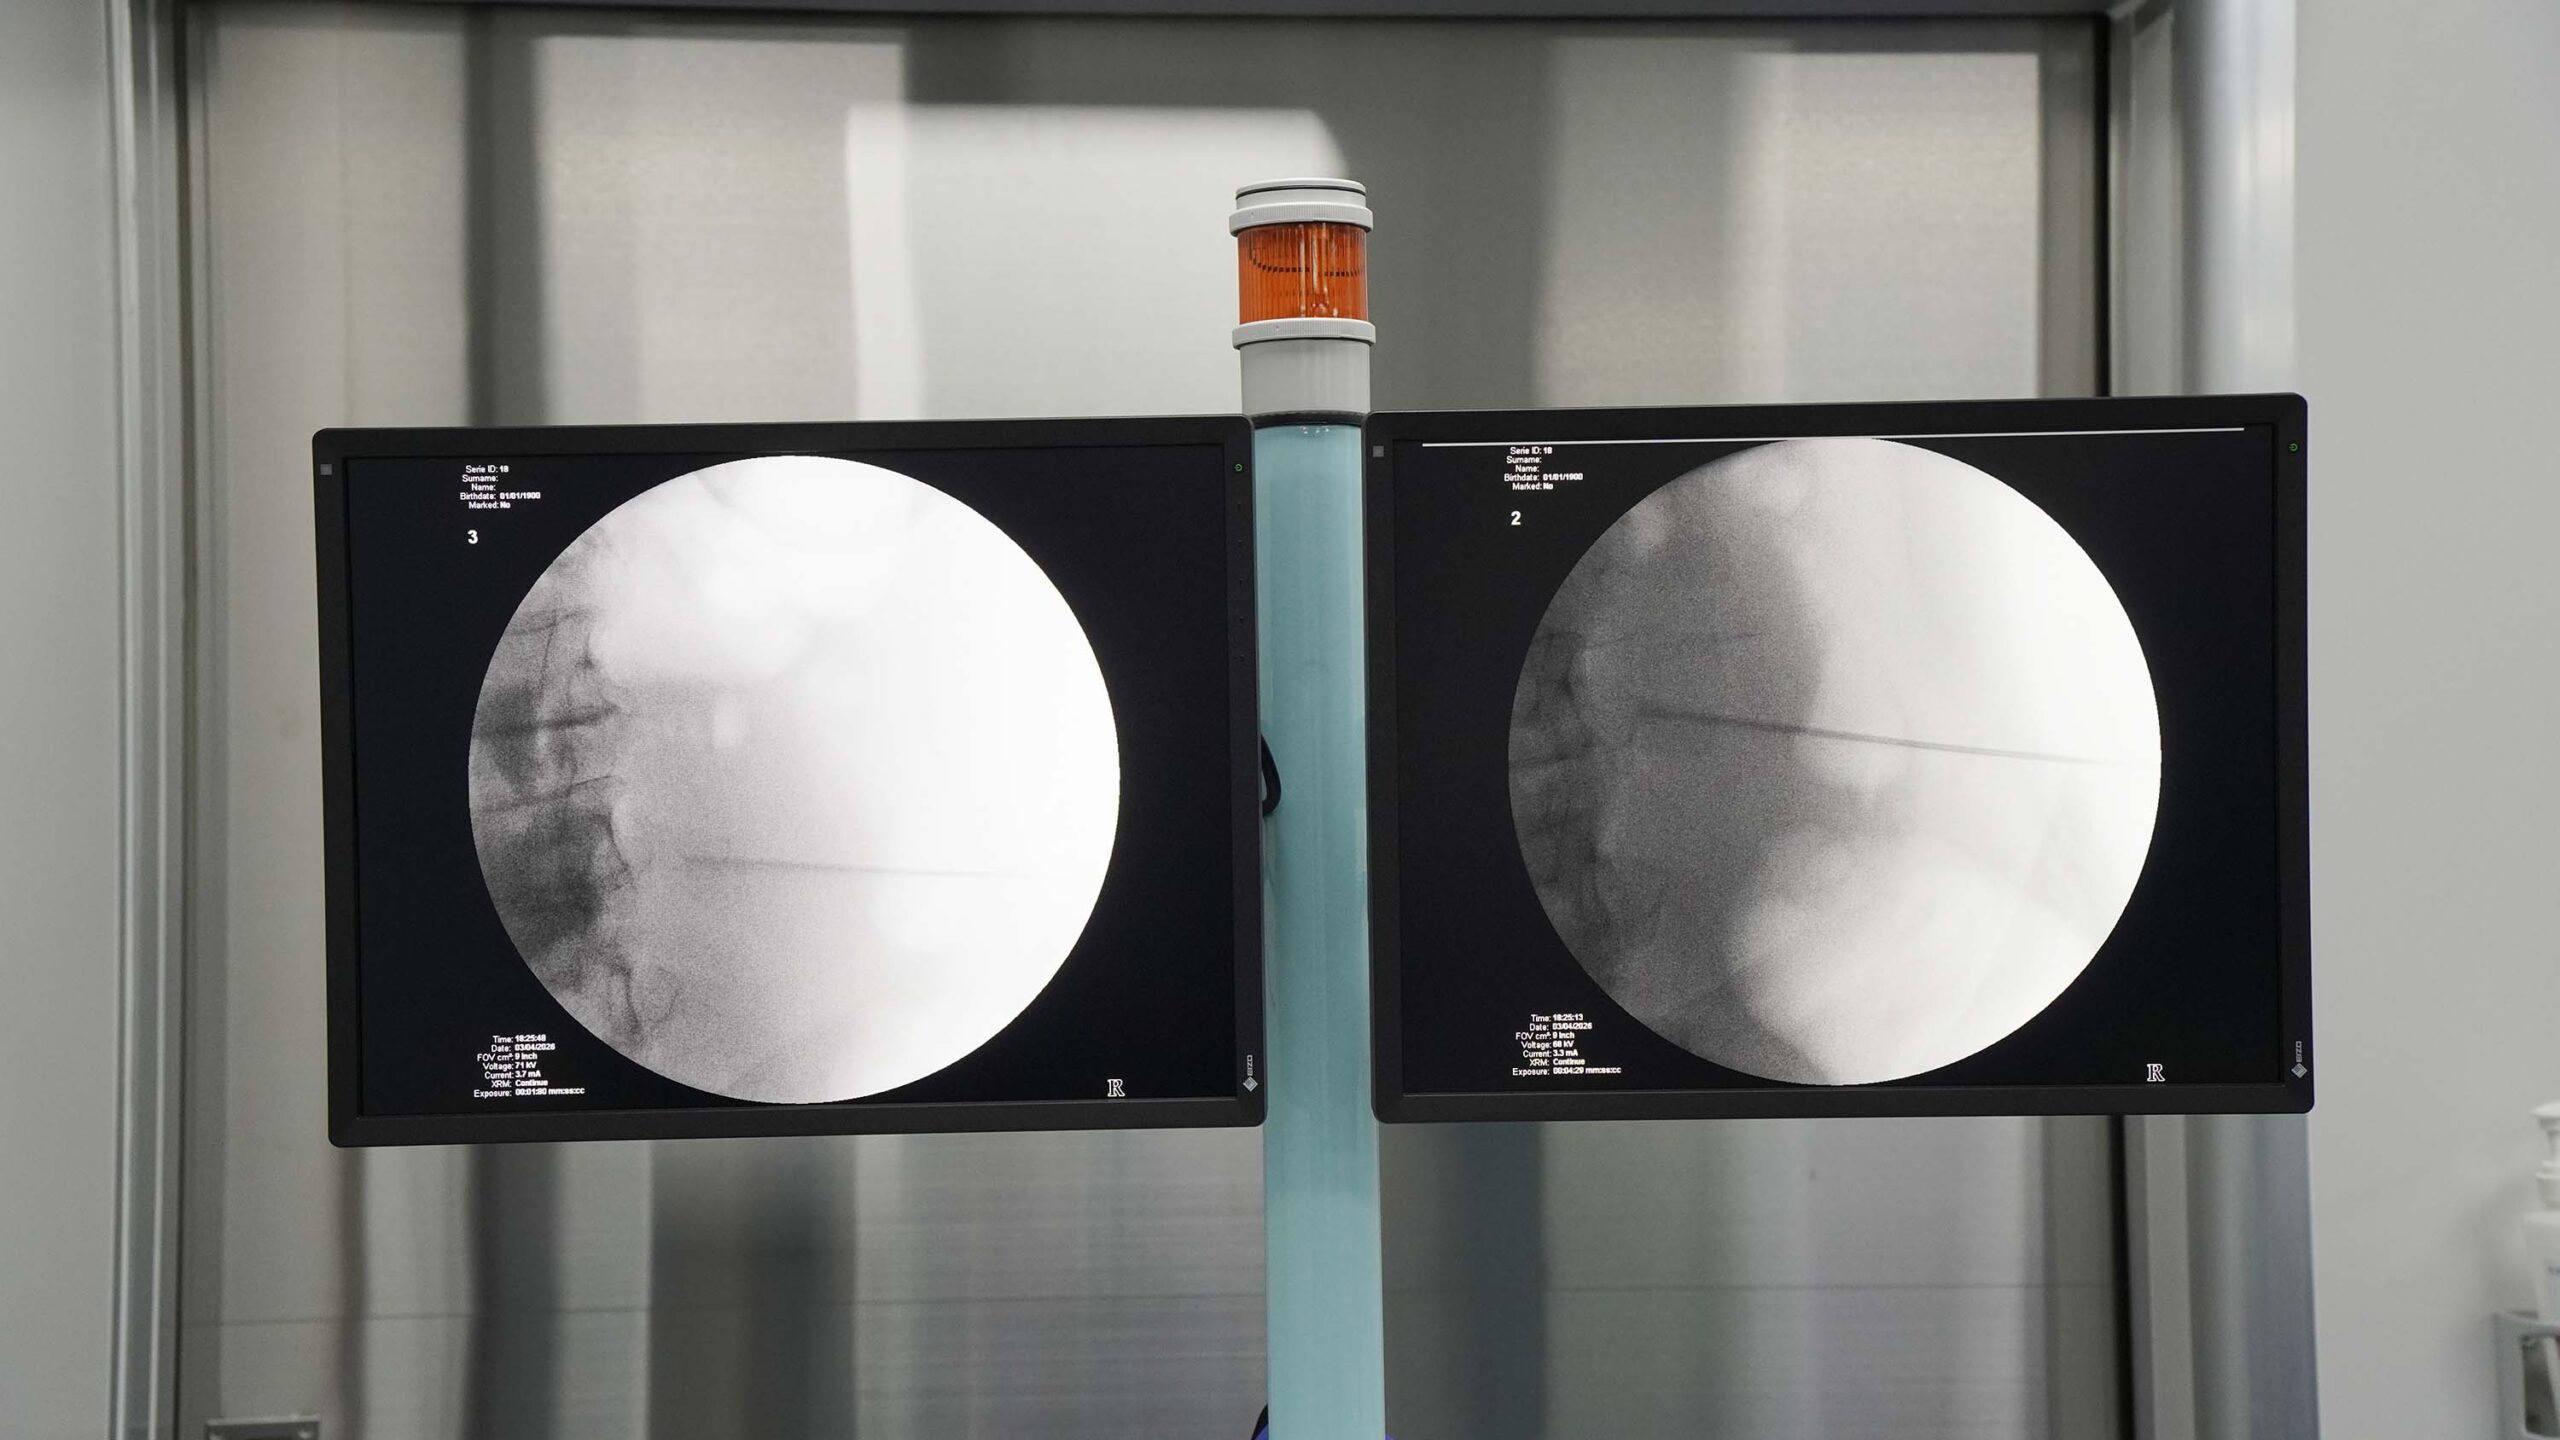

Không dừng lại ở đó, Bệnh viện ĐKKV Vân Đồn đã tiếp tục nâng cao chất lượng kỹ thuật bằng việc ứng dụng hệ thống C-Arm (màn hình tăng sáng) trong quá trình tán sỏi qua da. Đây là thiết bị chẩn đoán hình ảnh hiện đại, cho phép hiển thị cấu trúc bên trong cơ thể theo thời gian thực ngay trong khi phẫu thuật.

Nhờ sự hỗ trợ của C-Arm, bác sĩ có thể quan sát rõ ràng vị trí sỏi, hệ thống đài – bể thận cũng như toàn bộ quá trình đưa dụng cụ vào trong thận. Điều này giúp định vị chính xác đường chọc dò, tạo đường hầm an toàn, kiểm soát tốt từng thao tác can thiệp và xử lý sỏi một cách chủ động, chính xác hơn. Đồng thời, việc theo dõi liên tục trong suốt quá trình thực hiện giúp hạn chế tối đa tổn thương đến các mô lành xung quanh.